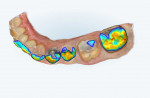

Following preparation, the margins were troughed using a diode laser (Picasso+®, AMD Lasers) with a 400-μm diameter tip that was set to deliver 0.5 W of power in the continuous wave mode. This was done to enable better visualization of the margins by the digital impression scanner. After laser troughing, the margins and preparation were digitally scanned, and the resulting "iRecord" file was visually inspected for integrity on the screen. Next, the occlusal surface was checked for proper reduction using the occlusal clearance tool included in the intraoral scanner's software. The occlusal clearance tool is applied after both arches are scanned and the teeth are imaged in maximum intercuspation. This tool determines the distance between the occlusal surface of the prepared tooth and the occlusal surface of the opposing dentition (Figure 6 through Figure 8) and lays out a color map indicating the proximity of the different areas of the surfaces (Figure 9). If inadequate reduction is noted, the preparation can be further reduced, and that area of the scan can be quickly and easily re-imaged to confirm that adequate reduction has been achieved and that the prosthesis will have adequate bulk to resist fracture during long-term occlusal loading.